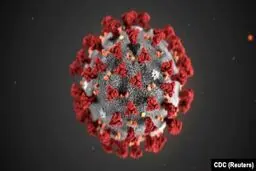

ضرورت بازسازی ستاد مقابله با کرونا

کرونا هرروز قربانی بیشتری میگیرد. نهتنها نقطه پایانی…